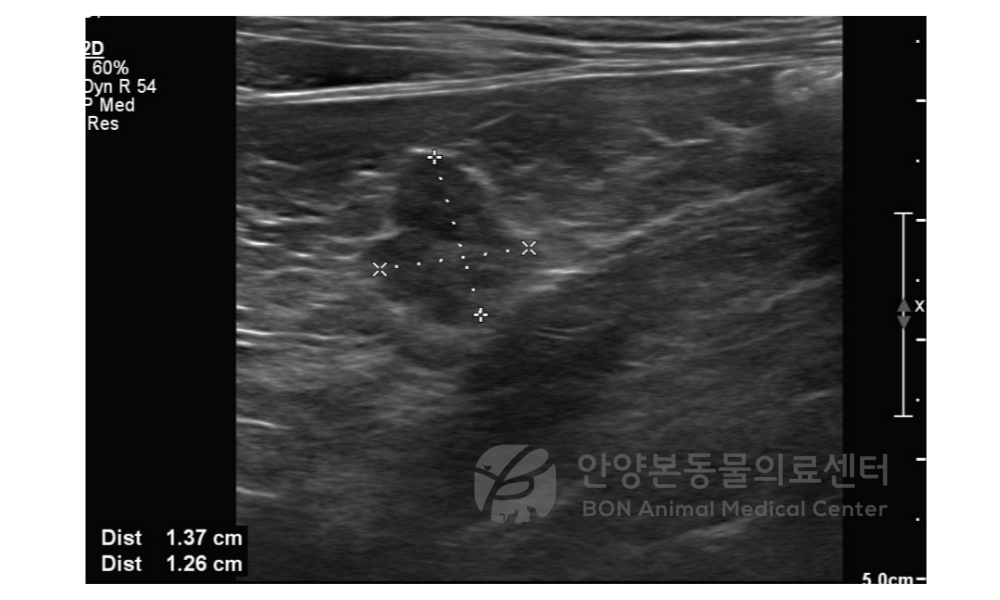

환자 상태 안정화 이 후 실시한 복부 초음파 검사 상 췌장 유래로 의심되는 종괴가 약 1.3cm 로 확인되며, 추가적으로 CT 검사를 진행하였습니다.

[복부 초음파 검사 결과]